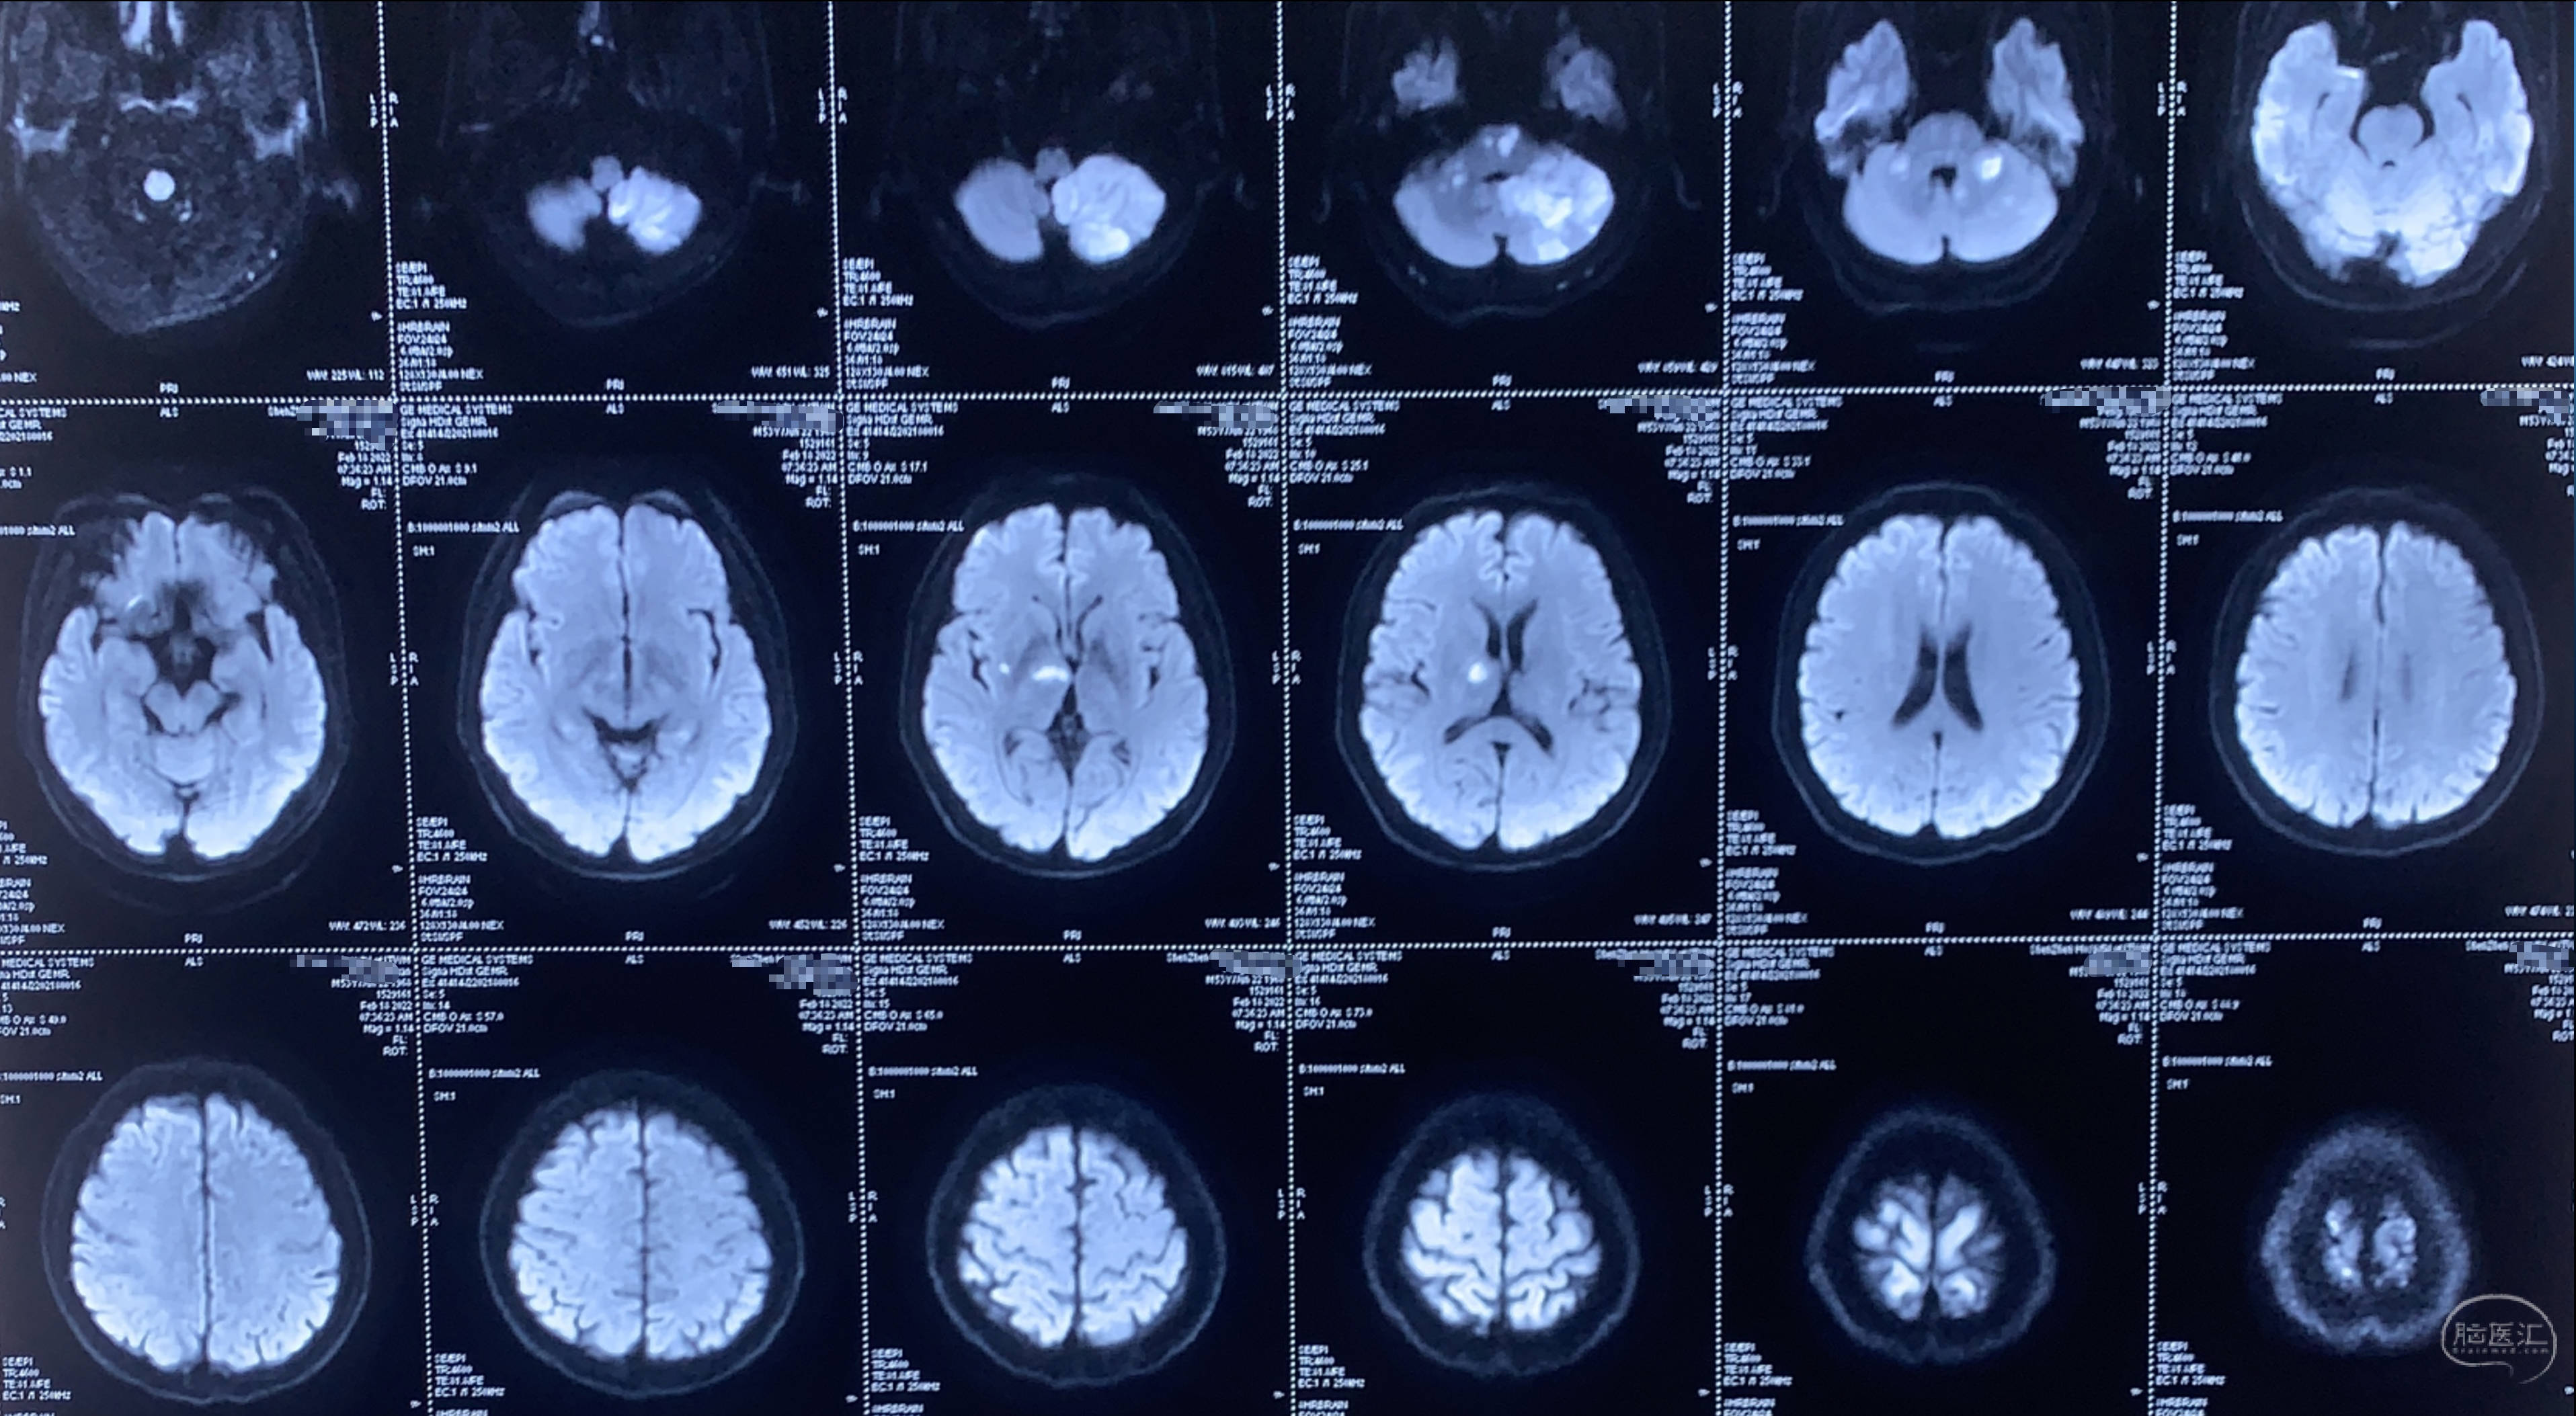

这是一个中年男性,头晕起病,外院MR提示后循环的多发梗塞!

MRA提示左侧椎动脉闭塞,右侧发育不良,颅内段重度狭窄。

入院后的CTA确认闭塞,右侧VA发育不良!

灌注CT提示后循环低灌注。患者头晕症状明显,手术意愿强烈,同时由于先前介入开通不成功的影响,排斥包括复合手术在内的介入治疗。在了解了枕动脉-椎动脉搭桥不需要开颅后,当即同意!